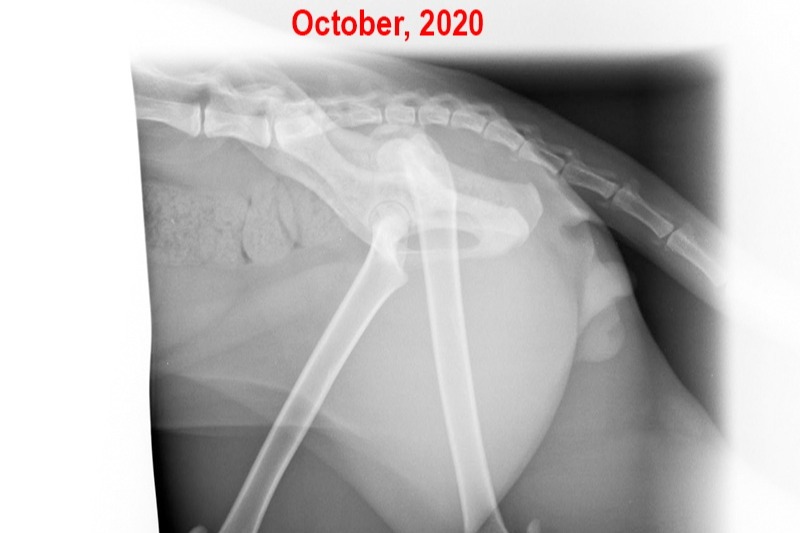

Below are Ziggy's X-Rays- The first set was taken when I first got him in October. The others were taken three months later. I don't really know how to read them, but the vet said they could see noticeable deterioration in that short time: